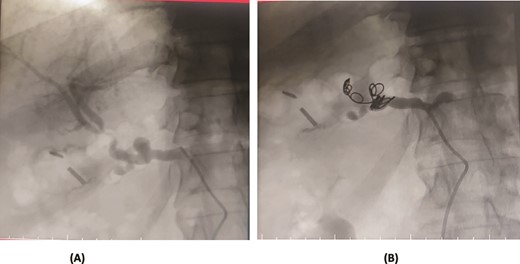

A 36-year-old female underwent a Whipple’s pancreaticoduodenectomy for pancreatic adenocarcinoma. On the fifth postoperative day, she experienced massive upper gastrointestinal bleeding, confirmed by endoscopy showing massive clots. A contrast-enhanced CT angiogram revealed a pseudoaneurysm from the proper hepatic artery, with abrupt truncation of the left gastric artery. Angioembolization was performed, with coil embolization of the proper hepatic artery and super selective embolization of the left gastric artery using gel foam. However, 32 days later, the patient experienced re-bleeding. A follow-up CT angiogram showed dislodging of the coil in the proper hepatic artery, allowing contrast through the coil and into the pseudoaneurysm. A second angioembolization repositioned the coil and used 70% glue and Lipiodol for embolization. Post-procedure, the patient had no further complications and was stable at follow-up (Fig. 3).

Case 3. (A) Angiogram shows pseudoaneurysm from proper hepatic artery. (B) Angioembolization of proper hepatic artery with coil.